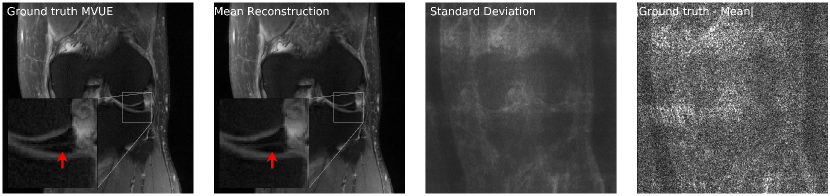

Refer to caption

Figure 4: Our method successfully recovers fine details and can provide an estimate of the reconstruction error. The left column shows a knee from the fastMRI dataset, along with an annotated meniscus tear (indicated by red arrow in zoomed inset). Given measurements at an acceleration factor of R=4𝑅4R=4, we obtain 484848 independent reconstructions via posterior sampling. The second column shows the pixel-wise average of reconstructions, the third column shows the pixel-wise standard deviation, and the fourth column shows the magnitude of the error between the ground truth and the mean reconstruction. Note that our generative prior has never seen such pathology, as it was trained on T2-weighted brain scans.

4.3 Uncertainty Estimation

Our method can also provide uncertainty estimates for each reconstructed pixel by running multiple reconstruction samplers. For a given observation y𝑦y, we can obtain independent samples x^1,,x^Kμ(|y)\widehat{x}_{1},\cdots,\widehat{x}_{K}\sim\mu(\cdot|y), for K𝐾K sufficiently large. Now, using the conditional mean estimate x¯=i=1Kx^i/K¯𝑥superscriptsubscript𝑖1𝐾subscript^𝑥𝑖𝐾\bar{x}=\sum_{i=1}^{K}\widehat{x}_{i}/K, we can compute the pixel-wise standard deviation i=1K|x^ix¯|2/Ksuperscriptsubscript𝑖1𝐾superscriptsubscript^𝑥𝑖¯𝑥2𝐾\sqrt{\sum_{i=1}^{K}|\widehat{x}_{i}-\bar{x}|^{2}/K}, and this gives an estimate of the error in each pixel. As shown in Fig 4, the pixel-wise standard deviation is a good estimate of the ground truth error |xx¯|superscript𝑥¯𝑥|x^{*}-\bar{x}|. Additionally, notice that the reconstructions are able to recover fine details such as the annotated meniscus tear222https://discuss.fastmri.org/t/219 in Fig 4 and predict low uncertainty for these features.

Figure 17 in Appendix D shows another example of an annotated meniscus tear. Figures 18 and 19 show comparisons with baselines on the same examples.